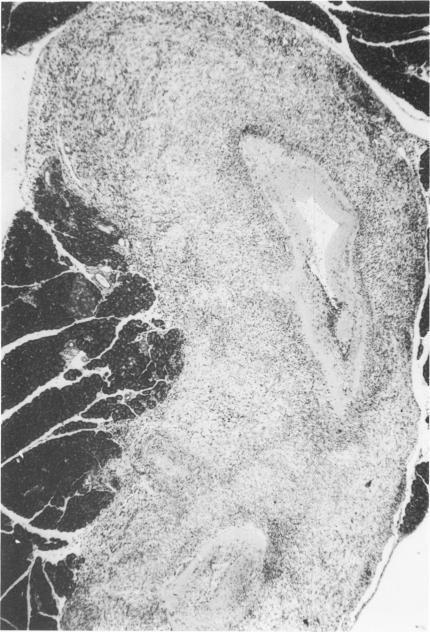

Normotensive, Sprague-Dawley (S-D) and spontaneously hypertensive (SH) rats were subjected to aortic ligature. The systolic blood pressure of S-D rats was increased by +/- 80 mm Hg, whereas the blood pressure of SH rats with pre-existent hypertension increased only slightly, +/- 9 mm Hg. The S-D rats developed myocardial and renal infarcts as well as polyarteritis nodosa; the SH rats developed testicular and microadrenocortical infarcts only. Aortic-ligated S-D rats had elevated creatine phosphokinase, serum glutamic-oxaloacetic transaminase, serum glutamic-pyruvic transaminase, and lactic hydrogenase levels and manifested hyperglycemia, hypercholesterolemia, and elevated blood urea nitrogen (BUN) levels. Corticosterone levels increased in aortic-ligated S-D rats but decreased in SH rats. Collateralization about the site of aortic ligature appeared to be the same in both strains. It is suggested that the acutely induced hypertension in S-D rats rather than SH rats and differences in adrenal steroidogenesis between the two strains would best account for the dichotomous cardiovascular response to aortic constriction.

对血压正常的斯普拉格-道利(S-D)大鼠和自发性高血压(SH)大鼠进行主动脉结扎。S-D大鼠的收缩压升高了±80毫米汞柱,而原本就患有高血压的SH大鼠血压仅轻微升高,为±9毫米汞柱。S-D大鼠出现了心肌梗死、肾梗死以及结节性多动脉炎;SH大鼠仅出现了睾丸梗死和肾上腺皮质微梗死。主动脉结扎的S-D大鼠肌酸磷酸激酶、血清谷草转氨酶、血清谷丙转氨酶和乳酸脱氢酶水平升高,出现高血糖、高胆固醇血症以及血尿素氮(BUN)水平升高。主动脉结扎的S-D大鼠皮质酮水平升高,但SH大鼠的皮质酮水平降低。两种品系大鼠在主动脉结扎部位的侧支循环情况似乎相同。有人提出,S-D大鼠而非SH大鼠急性诱导的高血压以及两种品系之间肾上腺类固醇生成的差异最能解释对主动脉缩窄的二分心血管反应。